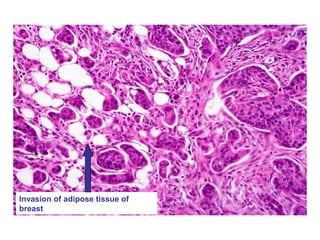

INFILTRATING DUCTAL

Infiltrating ductal carcinoma,

invading and replacing breast

stroma

Invasion of adipose tissue of

breast

Infiltrating ductal carcinoma, invadingand replacing breast stroma

Invasion of adiposetissue of breast